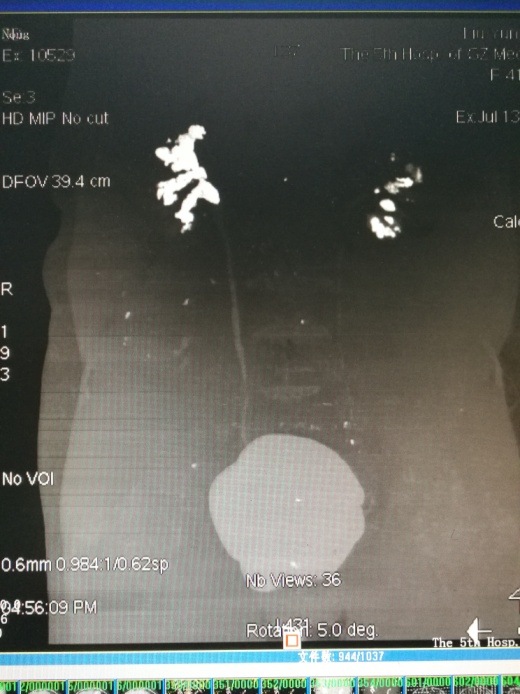

KUB

患者右侧肾结石分支肾盏多,肾盏狭长,这样的结石因为外形轮廓酷似‘鹿角’状,被称为“鹿角形肾结石”。同时她的左肾轻度萎缩,是典型的功能性孤立肾合并鹿角形肾结石。”结合入院的进一步完善检查和患者资料,李逊教授认为林阿姨此次手术难度大(取净结石难度大),手术风险高(手术出血风险高)。

肾盏分支多且肾盏狭长